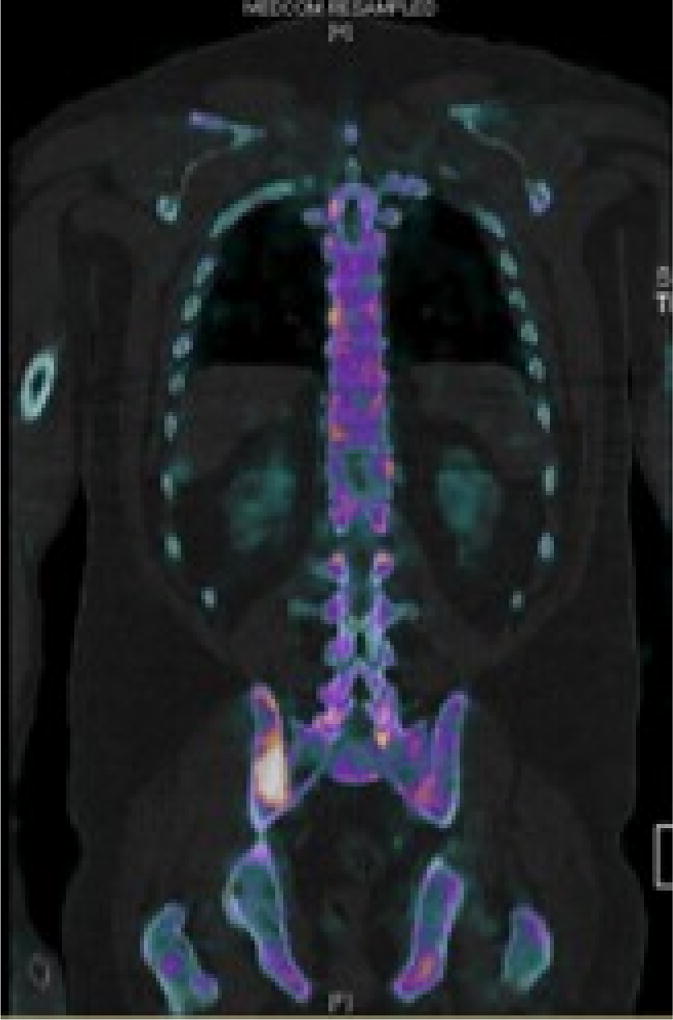

淋巴瘤表现为头皮肿块是一种罕见但严重的医学状况,需要积极治疗和神经外科干预。我们报告一个53岁的男性病例,他表现为右侧额部头皮肿块大,左侧额部头皮肿块小。在与患者讨论后,决定切除较大的肿块以确定诊断。肿块次全切除后,活检显示WHO 1级滤泡性淋巴瘤(FL),弥漫性IV期。患者随后接受了4格(Gy)的姑息性放疗,分2段对右侧额叶头皮进行放疗,并进行全身化疗免疫治疗(6个周期),随后进行了美罗华维持治疗。治疗开始一个月后进行腰椎穿刺取脑脊液,结果为恶性细胞扩散阴性。治疗开始约3个月后,PET/CT未显示活动性恶性肿瘤,MRI显示右侧额叶头皮肿物内部完全消退。我们用这个病例提供关于疾病病理生理,早期诊断和管理的详细讨论。

Lymphoma presenting as a scalp mass is a rare but serious medical condition mandating aggressive treatment and neurosurgical intervention. We report a case of 53-year-old male who presented with a large right sided frontal scalp mass and a smaller mass located on the left frontal scalp. After discussion with the patient, it was decided to resect the larger mass for definitive diagnosis. After subtotal resection of the mass, biopsy revealed WHO grade 1 follicular lymphoma (FL), diffuse pattern stage IV. The patient was subsequently treated with 4 grays (Gy) of palliative radiotherapy over 2 fractions to the right frontal scalp and systemic chemo-immunotherapy (6 cycles) followed by rituximab maintenance. Lumbar puncture to obtain cerebrospinal fluid was done a month after therapy began and the results were negative for spread of malignant cells. Approximately 3 months after initiation of therapy, PET/CT showed no evidence of active malignancy and MRI revealed a complete internal resolution of the enlarged right frontal scalp mass. We use this case to provide a detailed discussion regarding disease pathophysiology, early diagnosis, and management.